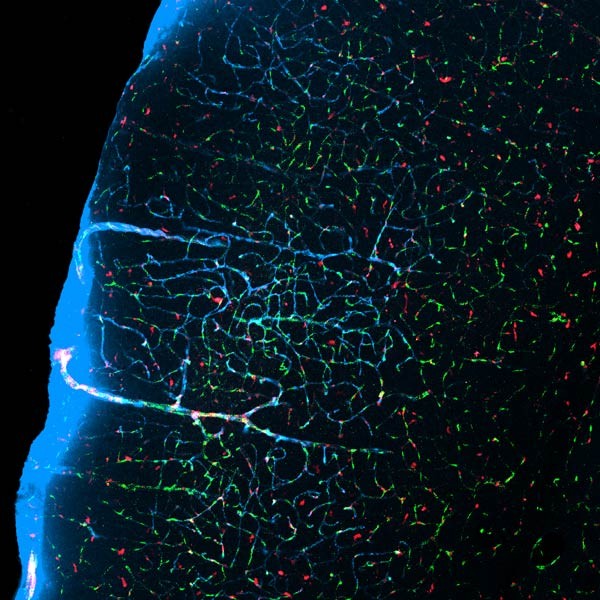

由于运输液体通过细胞膜需要大量能量,Nedergaard及其团队预测,大脑并不能同时完成清理和处理感觉信息的工作,于是他们决定测试睡眠期间类淋巴系统的活动是否会改变。该研究的第一作者Lulu Xie在接下来的两年中训练小鼠放松和睡眠,并在双光子显微镜(可以使染色物质通过活组织的运动成像)下观察。

Xie会观察小鼠的脑活动,一旦发现其进入睡眠状态,她便将绿色染料通过小鼠颈部一个像导管的设备注入到CSF中。半小时后,她通过触摸小鼠尾部使其清醒,并注入红色染料,双光子显微镜可以很容易地辨别这两种染料。Nedergaard称,通过追踪整个大脑中的红色和绿色染料,其团队发现在睡眠期间,大量CSF流入大脑,但是在清醒状态时却不会。

对小鼠清醒和睡眠时神经细胞间空隙大小的对比发现,睡眠时运载CSF的神经胶质细胞通道会扩张60%。研究团队还将作标记的β淀粉样蛋白注入到睡眠小鼠和清醒小鼠的大脑中,进而发现睡眠期间,CSF会很快地将这些“垃圾”清除到细胞外两次——“就像一个洗碗工”,Nedergaard这样形容。她说,这些蛋白质可以在细胞内聚合为致病性斑块,而且与阿尔茨海默氏症相关。